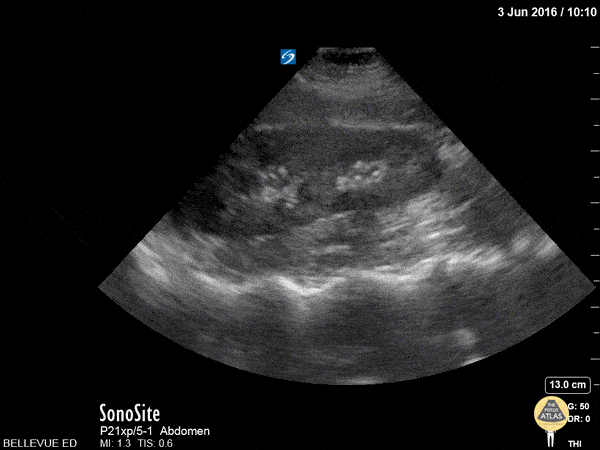

Renal/GU - RUQ Kidney Long Axis

This clip fans through the right kidney in long axis. The hyperechoic central area is the renal pelvis and calyces, the darker hypoechoic area surrounding it is the renal cortex. The darker/anechoic spots between the cortex and the medulla are renal pyramids. Deep to the kidney we see the hyperechoic spine. On the left of the screen and superior to the kidney is the liver which has a similar echogenicity to the renal cortex. Hannah Kopinksi and Dr. Lindsay Davis - NYU Emergency Medicine